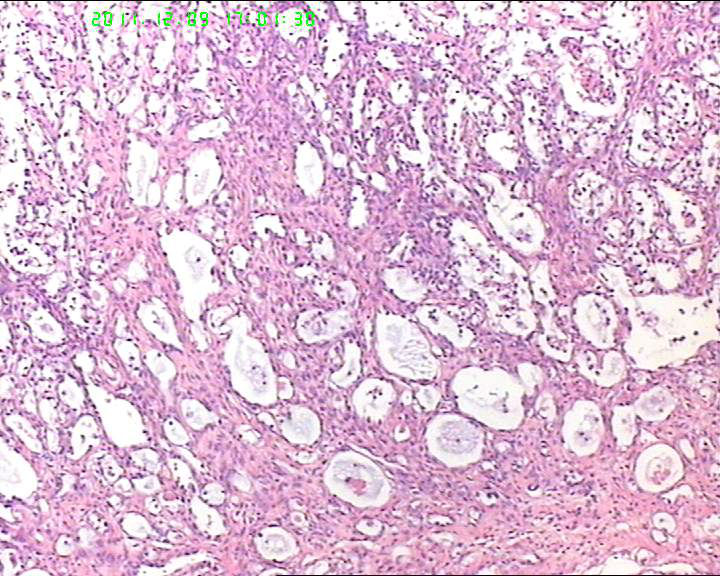

盆腔包块4个月,13*8*7cm 大小,囊实性,实性区菜花状、灰白质脆,局部半透明。

有腺腔样结构,内衬靴钉样细胞,还可见透明细胞,首先考虑透明细胞癌,鉴别诊断:内胚窦瘤。内胚窦瘤的网状结构内衬是扁平的上皮。

首先考虑透明细胞癌,鉴别卵黄囊瘤

筛状迷路样结构,部分呈乳头状,异型明显,S-D小体不明显,考虑卵黄囊瘤。做CK,AFP,AAT.